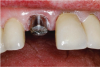

Fig. 9 through Fig. 11 The implant shifted slightly to mesial to avoid buccal concavity and bone graft. The implant was placed with a guide and a tissue punch was done, negating a flap. Figure 11 is the immediate postoperative photograph.